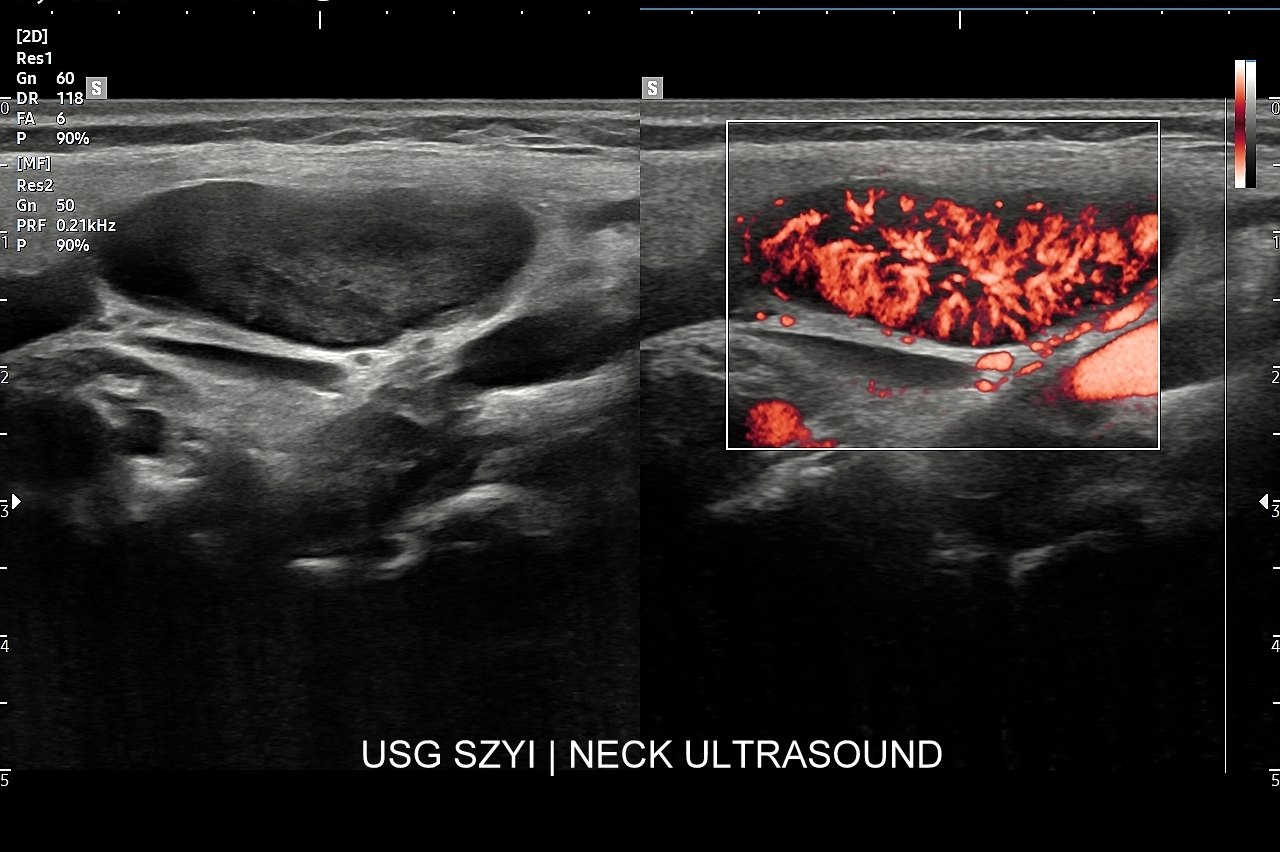

W Interdyscyplinarnej Pracowni USG dr Tomasza Szczepańskiego istnieje możliwość przeprowadzenia wysokospecjalistycznej oceny gruczołu tarczowego w postaci multiparametrycznego badania MPUS tarczycy, które wykonywane jest na zaawansowanym technologicznie aparacie USG przy wykorzystaniu modalności zwiększających rozdzielczość obrazowania zmian chorobowych oraz wnoszących istotne, dodatkowe dane kliniczne dotyczące zmian patologicznych w organie. Badanie MPUS tarczycy jest szczególnie przydatne w przypadku diagnostyki i oceny guzków tarczycy oraz ich kwalifikacji do dalszego postępowania. Nowoczesne modalności MPUS, o których mowa, obejmują w szczególności badanie dopplerowskie miąższu gruczołu, ocenę dopplerowską tętnic tarczycowych, badanie mikroprzepływów  MVF oraz elastografię.

Czemu służy badanie CEUS tarczycy? Badanie USG z użyciem opcji multiparametrycznych, takich jak Doppler, mikrounaczynienie (MVI) i elastografia w większości przypadków stanowi wystarczającą kombinację diagnostyczną w celu oceny guzków tarczycy w skali TIRADS i ich kwalifikacji do ewentualnej biopsji cienkoigłowej. W wyselekcjonowanych przypadkach badanie USG tarczycy z kontrastem (CEUS) może jednakże wnieść dodatkowe i istotne klinicznie informacje, np. czy dany guzek / zmiana ogniskowa ma charakter zmiany unaczynionej, czy nieunaczynionej; albo wykazanie ukrytych cech złośliwości guzka.